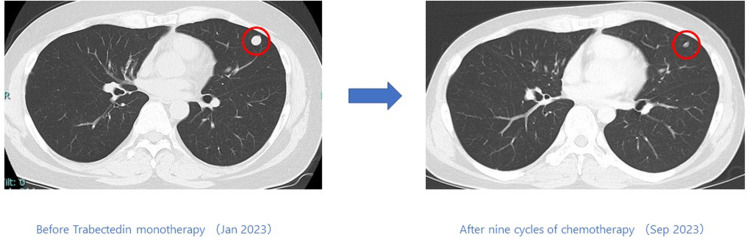

Case presentation: Case 1: A 44-year-old male started trabectedin as second-line therapy after initial chemotherapy, which included doxorubicin. To date, he has completed 9 cycles, showing a response for 6 months. Case 2: A 71-year-old male, deemed intolerant to doxorubicin, started trabectedin as his first-line treatment. He has undergone 50 cycles to date, maintaining a response for 56 months. Case 3: A 59-year-old female began trabectedin as second-line therapy after initial chemotherapy, including doxorubicin. She responded for 6 months before experiencing disease progression. Case 4: A 79-year-old male developed new lesions after one course of initial chemotherapy, including doxorubicin. He then began trabectedin and has maintained a response for 10 months to date.

背景:肌样脂肪肉瘤是一种罕见的肿瘤类型,约占所有脂肪肉瘤的30%。在基础研究和一些临床实验中,携带 FUS/CHOP 融合基因的类粘液性脂肪肉瘤使用曲贝替定取得了良好的效果。然而,曲贝替定对未接受化疗的软组织肉瘤或FUS/CHOP融合基因阳性的肌样脂肪肉瘤的有效性和安全性尚未确定。因此,我们评估了本院四例携带FUS/CHOP融合基因的类粘液性脂肪肉瘤患者接受曲贝替定单药治疗的有效性和安全性:我们分析了在冈山大学接受手术并在川崎医学院接受化疗的四例转移性肌样脂肪肉瘤患者。这些患者的 FUS/CHOP 融合基因检测结果呈阳性,通过 RT-PCR 技术辅助病理诊断。从冷冻肿瘤标本的肿瘤组织切片中提取 RNA。反转录后,使用 TLS/FUS-CHOP 引物进行 PCR。对得到的产物进行电泳,然后确认核苷酸序列:病例 1:一名 44 岁的男性患者在接受了包括多柔比星在内的初始化疗后,开始接受曲贝替定作为二线疗法。迄今为止,他已完成了 9 个周期的化疗,并在 6 个月内出现了反应。病例 2:一名 71 岁的男性患者被认为不能耐受多柔比星,他开始接受曲贝替定作为一线治疗。迄今为止,他已接受了 50 个周期的治疗,56 个月来一直保持着应答。病例 3:一名 59 岁的女性患者在接受了包括多柔比星在内的初始化疗后,开始将曲贝特林作为二线疗法。她在治疗 6 个月后病情出现进展。病例 4:一名 79 岁的男性患者在接受了包括多柔比星在内的一个疗程的初始化疗后出现了新的病变。随后,他开始接受曲贝替定治疗,迄今已有10个月的应答:结论:与其他化疗方法相比,曲贝替丁(Trabectedin)对携带FUS/CHOP融合基因的肌样脂肪肉瘤患者具有潜在的更高疗效和良好的安全性。